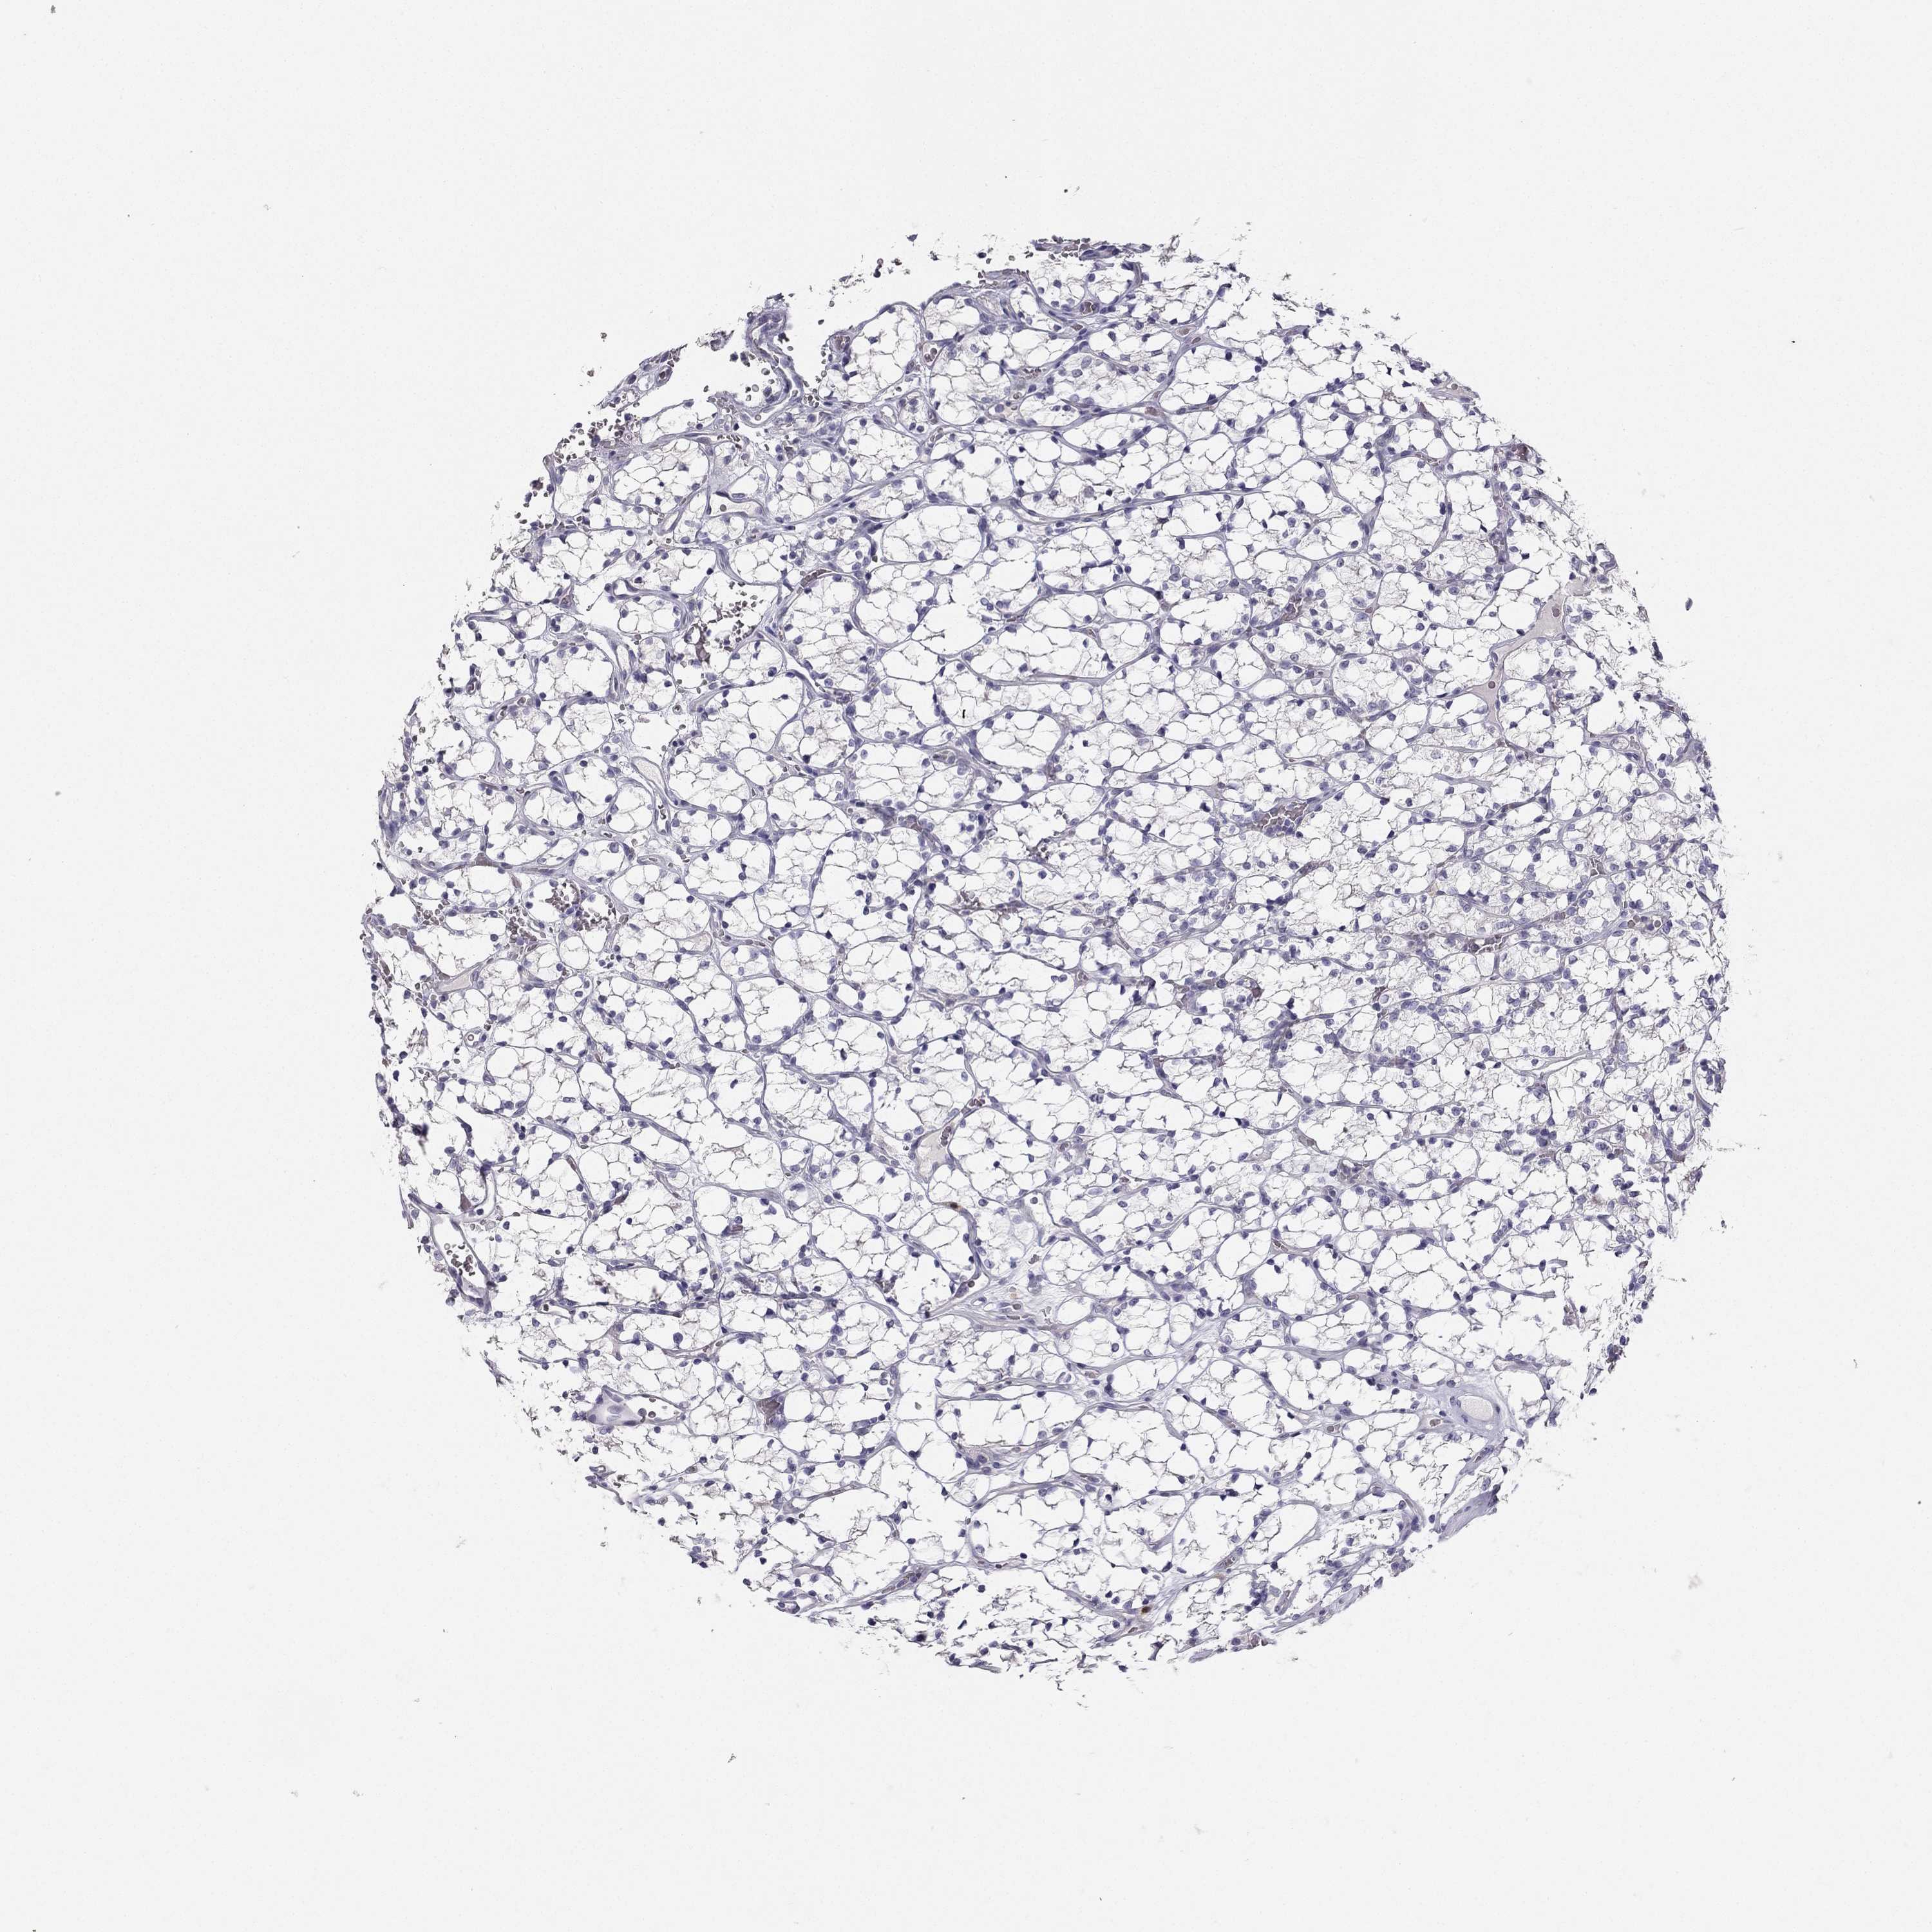

Average pTPM 0.2

Number of samples 64